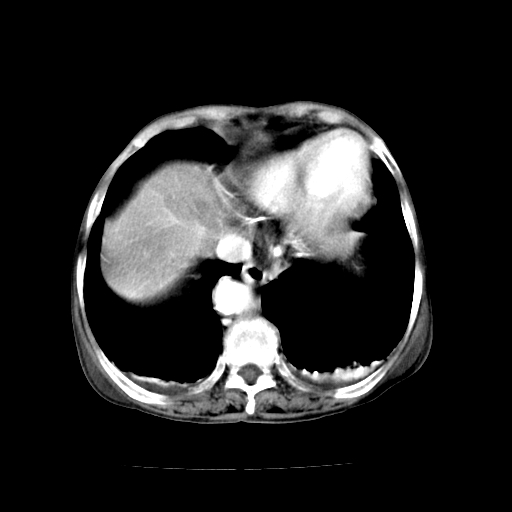

女,68岁,腹胀、恶心两周,先做ct平扫,当时家属不同意强化,6天后家属要求增强扫描。

1、胃窦癌; 2、局灶性脂肪肝。

1、胃窦癌?建议行胃镜!; 2、局灶性脂肪肝。

支持考虑1、胃窦癌?建议行胃镜!; 2、局灶性脂肪肝。  3、双侧胸腔积液,胸膜增厚